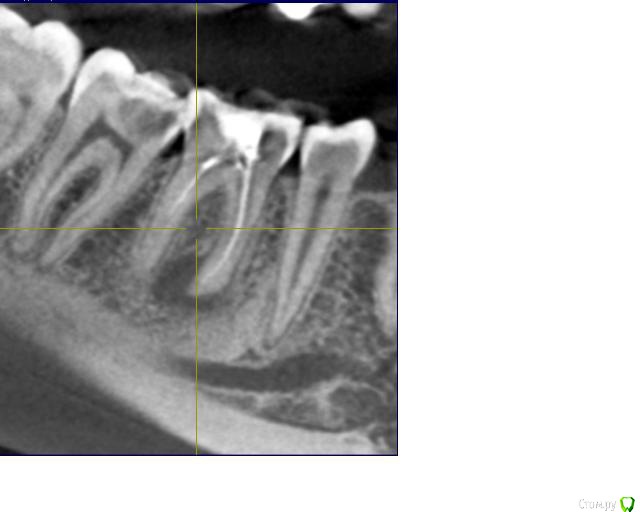

Ксения_ Опубликовано 27 августа, 2015 Поделиться Опубликовано 27 августа, 2015 (изменено) Здравствуйте Уважаемые Доктора! КТ сделано 4 мес назад. После этого пролечен кариес 14, 16, 37, 35. Пролечен пульпит 25, 36.Осталось пролечить пульпит в 15, 26, 47. Удалить все восьмерки.Далее ортодонтия. Стоит вопрос об удалении 46. Зуб ранее был пролечен другим врачом некачественно (+ пропущен канал).Мой лечащий доктор, после консультаций с коллегами, предлагает удаление, т.к. с его слов прогноз у этого зуба неблагоприятный (считает, что через пару лет процесс повторится) и смысла в столь дорогом лечении нет. Мне, конечно, хотелось бы по возможности зуб сохранить.Как вы считаете какой прогноз у этого зуба? P.S. Зуб не беспокоит. Точнее ни один зуб у меня вообще ни разу в жизни не болел (несмотря на такое количество пульпитов, которые для меня были неожиданностью. Врачу своему доверяю.). Несколько докторов которые меня смотрели считают, что у меня высокий болевой порог. Изменено 27 августа, 2015 пользователем Ксения_ Ссылка на комментарий

M@estro Опубликовано 27 августа, 2015 Поделиться Опубликовано 27 августа, 2015 (изменено) Судя по рентгену - прогноз благоприятный. Зуб сохранен,это главное. "процесс повторится" - на это при современном подходе выделяют не более 5 % .Если бы у меня 95 % вероятности в казино было - я бы дом поставил , не то что зуб полечил ) Ключевое при перелечивании - соблюдение современного протокола лечения. P.s. После лечения уже больше двух лет прошло,недавно был на осмотре - процесс все никак не повторится )) Изменено 27 августа, 2015 пользователем M@estro 3 Ссылка на комментарий